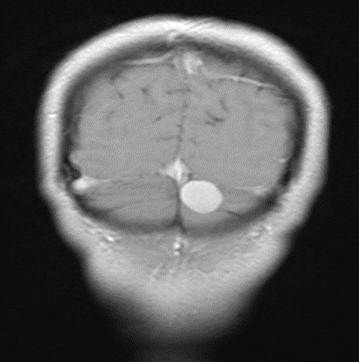

才到当地医院做了头颅MRI等检查

“你左侧后脑勺里,可能有个脑肿瘤。”

结合李姐头晕多年的病史

神经外科主任范学政告诉她:

“这可能是脑膜瘤, 必须手术切除

它位置刁钻,正好处在静脉回流交汇处、横窦旁”

术后病理提示,李姐脑中的是脑膜瘤。

这是颅内发病率第二的原发性肿瘤,而且好发于中年女性,脑膜瘤早期症状不明显,初期仅有头痛头晕症状,很容易被忽视,所以脑膜瘤被发现时往往已经长得很大。

但好在脑膜瘤没那么可怕,它们绝大多数是良性的,且预后很好,但是不同部位的脑肿瘤,引发的症状也不同,像李姐的反复头晕。